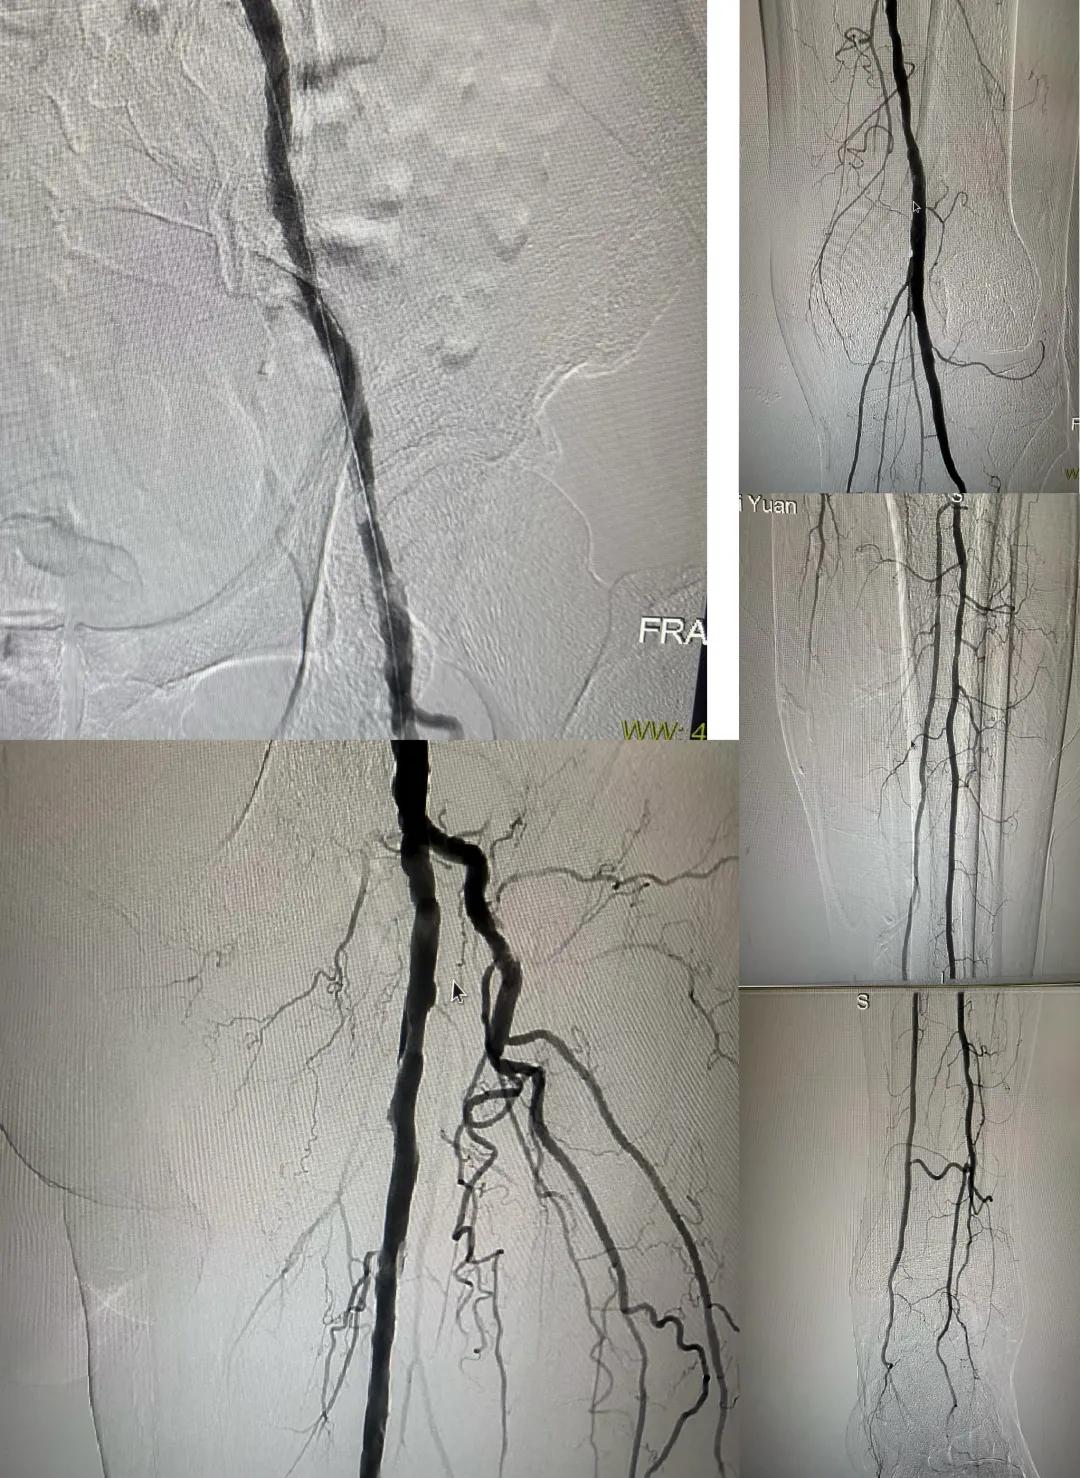

患者,男,73歲,約15天前出現(xiàn)左側(cè)腳面腫痛,間歇性跛行,左足第三足趾壞疽,遂來市中醫(yī)院就診,以“下肢動(dòng)脈硬化閉塞、糖尿病足壞疽、”收住外二科,評(píng)估患者病情后需實(shí)施左下肢球囊擴(kuò)張成形術(shù)。術(shù)中造影見患者左側(cè)髂動(dòng)脈、股淺動(dòng)脈階段性重度狹窄。經(jīng)外周球囊擴(kuò)張術(shù)后,再次造影見股淺動(dòng)脈、髂動(dòng)脈血流通暢,膝下及足部血流速度較前改善。

術(shù)后已疏通血管成像

從術(shù)后緩解癥狀到長(zhǎng)期的健康益處,手術(shù)不僅是血管解剖結(jié)構(gòu)的修復(fù),更是患者整體健康的轉(zhuǎn)折點(diǎn)。